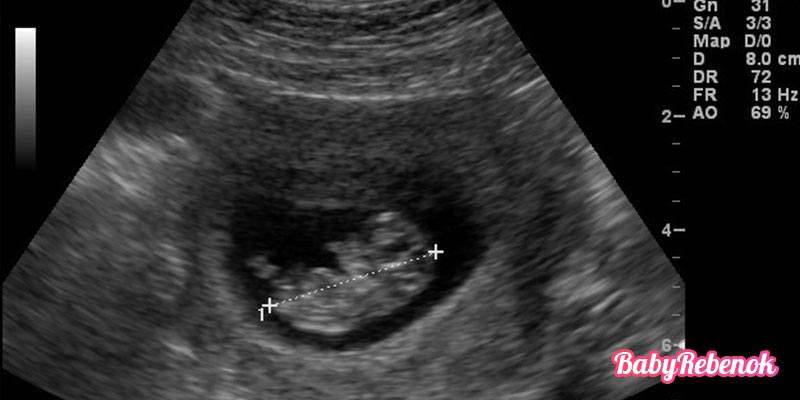

Что покажет УЗИ на 10 неделе беременности. Фото плода

На 10 неделе беременности обычно не проводят УЗИ без каких-то особенных показаний. Обычно контрольное исследование назначают на период между 10 и 14 неделями. Но если сделать УЗИ на 10 неделе, можно увидеть, что плод уже похож на человека. Если он не спит, то активно шевелится, двигает ручками и ножками, может брать пальчик в рот. Плод находится в пузыре, наполненном амниотической жидкостью.

Фото УЗИ на 10 неделе беременности

Идеальное время для проведения УЗИ на 10 неделе беременности – это примерно с 9 по 12 неделю. В этот период можно увидеть малыша, услышать его сердцебиение и оценить развитие плода.